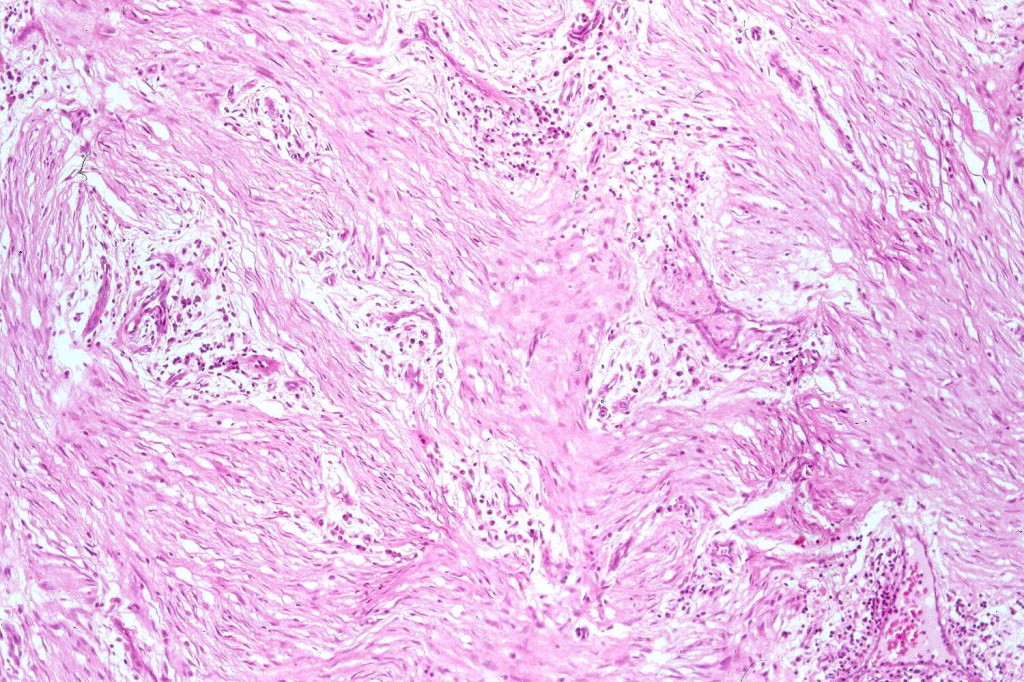

Cellular blue nevus

This uncommon most often devlops on the buttocks, sacrococcygeal region & distal extremities although it may be seen at just about any site. It shows a predilection for females and is diagnosed most often in the 2nd-4th decade. It presents as a blue-black/ or black nodule measuring 1-2 cm in dianeter. Similar to common blue nevus, the cellular variant can be encountered in a wide range of non-cutaneous locations.

Histological features

•Most characteristic is the dumbbell silhouette although a plague morphology may also be encountered

•Admixture of spindle cells, pigmented bipolar or dendritic cells & melanophages

•Cytoplasm is pale and nuclei are small with inconspicuous nucleoli

•An alveolar pattern is characteristic particularly with clear cell nodules

•Stromal fibrosis, myxoid change, vascular hyalinization with cyst formation are often seen

•Some tumors are composed spindle cells in a fascicular or neuronevoid pattern